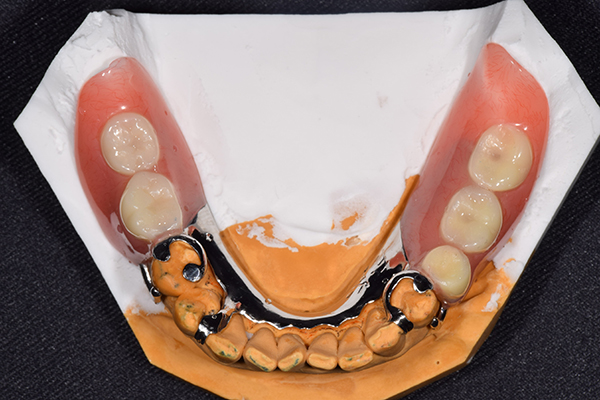

ケース2(自費の総入れ歯と部分入れ歯)

上下の入れ歯が外れやすくなったということでいらっしゃいました。 顎の骨はしっかりしていましたので、精密な型取りさえすればしっかりした入れ歯がつくれると思いました。 また下には6本歯が残っていましたが、虫歯になっている歯もありました。 かぶせ物のなかで大きな虫歯があった歯があり、1本だけ残せない状態でした。

上の入れ歯は確かに吸着は甘くなっていました。 また下の入れ歯はバネの一部が壊れており、安定感がなくなっていました。

精密な型取りの後、噛み合わせのチェックをしていきました。 かぶせ物も同時に作っていきました。

歯を並べた後、かぶせ物のフレーム作ってもらいました。先に歯を並べて理想の位置を決めておくことが大切です。

完成した入れ歯とかぶせ物です。 入れ歯への寛容度が高い患者様でしたので、 金属は使用せず、プラスチックのみで上は仕上げました。 下顎も歯は1本減ってしまいましたが、しっかり 入れ歯が維持できる様な構造にしました。

お口の中に入れた状態です。 見た目も最初とほとんど変わることなく作成できました。 維持や吸着に関しても問題ないようでした。